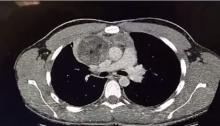

Methods: A 17-year-old male presented with chest pain and was examined preoperatively by chest x-ray, computed tomography of the chest with contrast, and a CT guided biopsy of the mass. The chest CT revealed a mass in the anterior mediastinum adherent to the right upper lobe invading the pericardium and compressing the superior vena cava and innominate vein. Pathological analysis of the biopsy revealed a non-malignant mature teratoma with keratinizing squamous epithelium with adnexal structures (skin), respiratory epithelium, intestinal epithelium, pancreatic tissue, cartilage, adipose tissue, and thymic tissue.